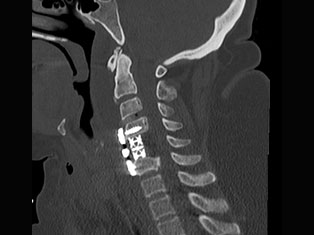

Degenerative Spine

The phrase "degenerative changes" in the spine refers to osteoarthritis of the spine. Osteoarthritis is the most common form of arthritis. Doctors may also refer to it as degenerative arthritis or degenerative joint disease.